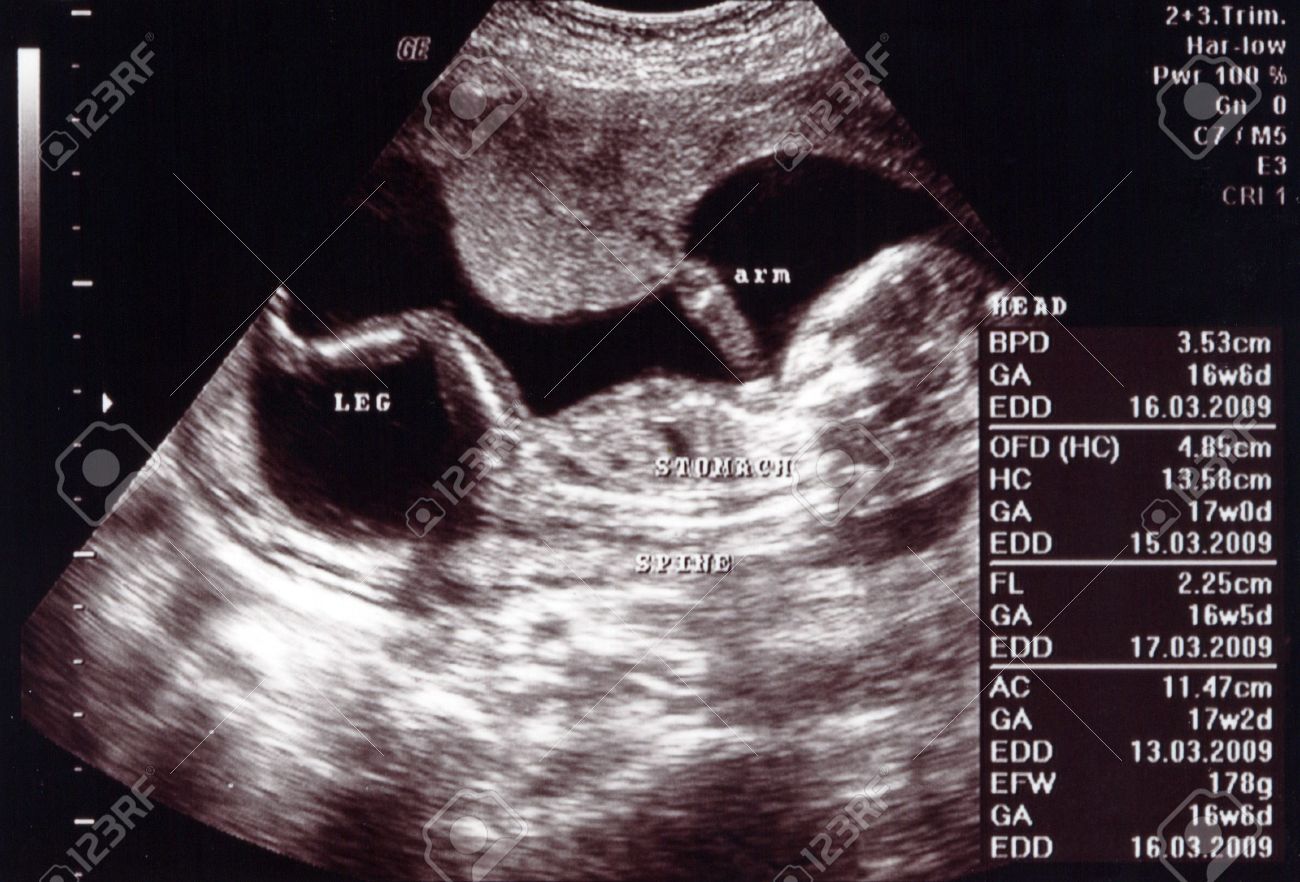

Ultrasound At 17 Weeks. Why an Ultrasound at 17 weeks is Important Controlling the placenta and umbilical cord. Find out the exciting new developments happening during this part of. While most practitioners will wait until at least six weeks to perform the first ultrasound the gestational sac may be seen as early as four and a half weeks while a heartbeat may be detected as early as five. This two structures are now more visible and well-developed.

Due to fetal position and size some of the views at 17 weeks can be suboptimal that means that they are not 100 clear if this is the case a follow up Ultrasound will be recommended at week 20.

I have an appt on July 21st to see if we can see the sex of the baby. Between weeks 18 and 20 a trained sonographer will perform a detailed anatomy scan called a level 2. According to what I had been told at my OBGYN that I was 16 weeks yesterday at the hospital they told me I was 17 weeks. I am just so excited and cant wait any longer. So i made an appointment at First Peek Ultrasound. While most practitioners will wait until at least six weeks to perform the first ultrasound the gestational sac may be seen as early as four and a half weeks while a heartbeat may be detected as early as five.